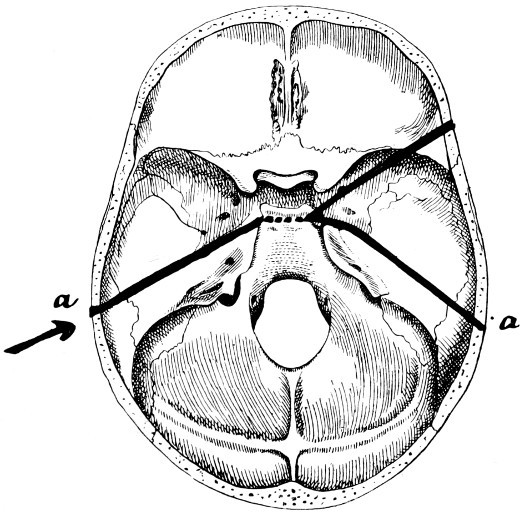

28. Illustrating the lines along which forces received on the vault are transmitted to the base 69

29 A and B. The base of the skull and the base as seen on transillumination 70, 71

30. Plan of the base of the skull 77

31. To illustrate the relation of basic fractures to cranial nerves 81

32-37. The lines pursued by basic fractures 83-8